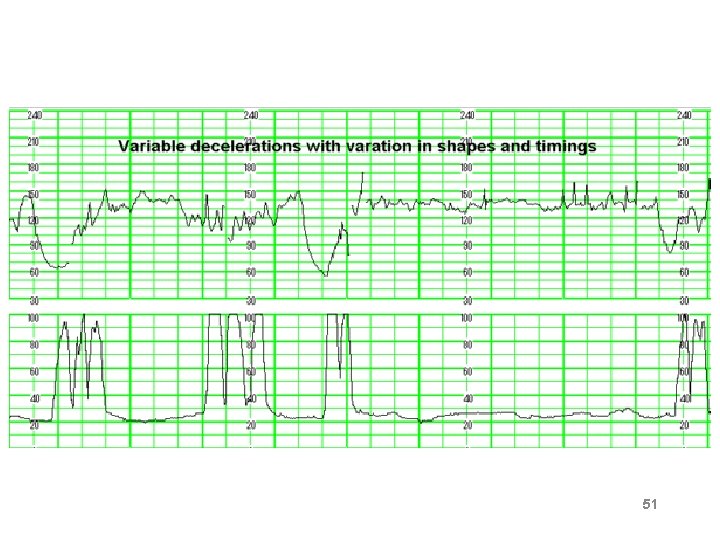

Variable Deceleration Abrupt decrease in FHR of > 15 beats per minute measured from the most recently determined baseline rate. The onset of deceleration to nadir is less than 30 seconds. The deceleration lasts > 15 seconds and less than 2 minutes. A shoulder, if present, is not included as part of the deceleration. Variable decelerations may be observed in up to 50% of NSTs. If nonrecurrent and <30 seconds, they are of no clinical significance.

Variable Deceleration Typical: • shoulders Atypical : • Overshoot • Loss of primary shoulder • Slow return to baseline (late component) • Baseline returns to a lower level(after deceleration) • Biphasic(W shape) • loss of variability during deceleration

Classification severity of variable deceleration • Mild: duration < 30 second or depth up to 80 bpm • Moderate : deceleration < 80 bpm • Severe : deceleration < 70 bpm for more than 60 second

Complicated variable deceleration Indicated fetal hypoxia • Tachycardia • Lack of variability • Slow return to baseline • Large amplitude(to 60 bpm or duration 60 second) • Loss of pre and post shouldering • Smooth overshoot

51